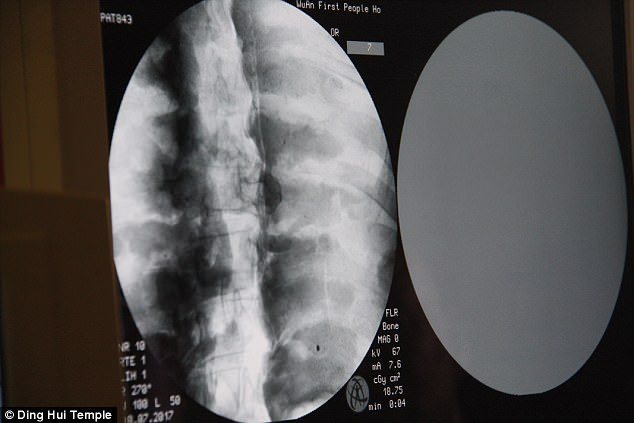

Vào năm 2017, các chuyên gia tiến hành chụp CT cho xác ướp mạ vàng thiền sư Ci Xian nổi tiếng Trung Quốc. Cuộc kiểm tra được tiến hàng ngay tại chùa Dinghui, ở Vũ Hán, phía bắc tỉnh Hà Bắc.

Kết quả chụp CT cho thấy thi hài của thiền sư Ci Xian còn nguyên vẹn đến mức khó tin.

Đặc biệt, hàm trên, răng trên, xương sườn và các khớp của thiền sư Ci Xian vẫn hoàn chỉnh giống như của người mới qua đời.

Điều này cho thấy xác ướp thiền sư Ci Xian ở trong tình trạng rất tốt, không có dấu hiệu bị phân hủy.